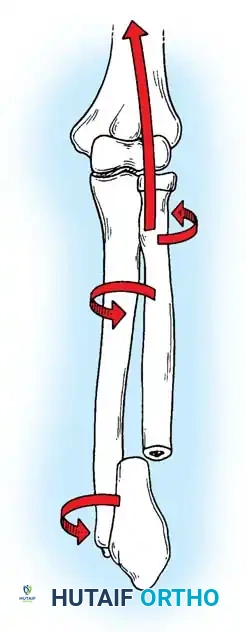

Biomechanics of the Tension Band:

The superficial (posterior) surface of the olecranon is the tension side of the bone. A figure-of-eight wire placed on this surface converts the tensile forces generated by the triceps into compressive forces across the articular fracture line, utilizing the humeral trochlea as a fulcrum.

Surgical Warning: A simple wire loop is biomechanically inferior to a figure-of-eight loop. If a simple loop is used—especially if its axis lies anterior to the mid-axis of the olecranon—the pull of the triceps will cause the fragments to separate posteriorly, leading to articular step-off and limited extension.